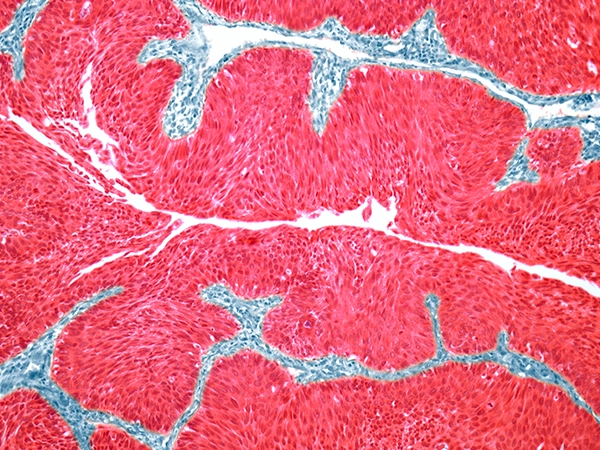

Hematologic malignancies, like lymphoma and multiple myeloma, impact blood cells.7